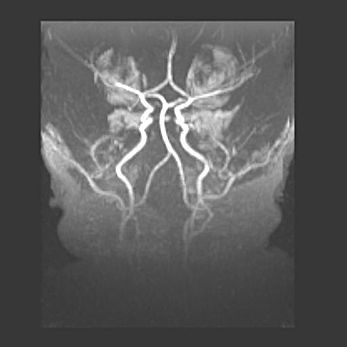

Мальформация Денди-Уокера. Киста задней черепной ямки.

Агенезия мозолистого тела.

Возраст: 2,5 месяца

Вес: 2420 г

Пол: женский

Окружность головы: 37 см

Срок гестации: 32 недели

Мальформация Денди—Уокера — редкий вид патологии ЦНС, представляющий собой врожденный порок развития каудального отдела ствола и червя мозжечка, ведущий к неполному раскрытию срединной (Мажанди) и латеральных (Лушка) апертур IV желудочка мозга. Для этогно синдрома характерна триада симптомов: гипотрофия червя мозжечка и/или полушарий мозжечка, кисты задней черепной ямки, гидроцефалия различной степени. В 70% случаев порок сочетается и с другими аномалиями головного мозга, в частности с агенезией мозолистого тела.